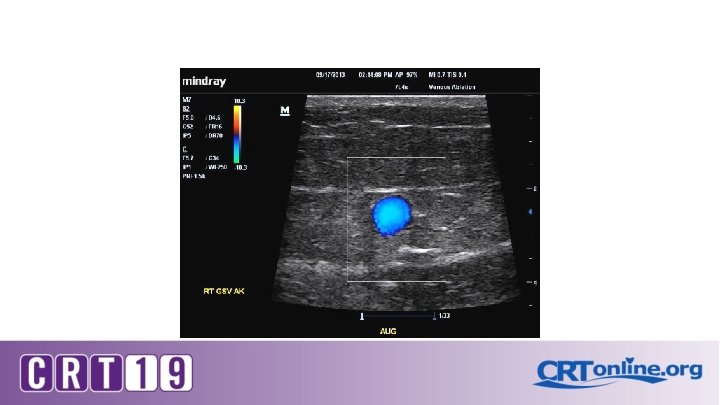

Ultrasound Diagnostic Study � Required in order to determine the source of reflux � Evaluate for venous occlusion or thrombus � Map the course of the incompetent superficial veins

On Ultrasound: Grey scale , color and Doppler Compressibility Phasic flow Augmentation Perforators Reflux and its duration Vein diameters

Diagnostic testing for Venous insufficiency CVI Venous Doppler *technique* S. V. reflux >3 secs Stasis ulcer Stasis dermatitis S. V. reflux >3 secs Deep vein reflux No reflux Vein diameter Symptoms Compression stockings Ablation